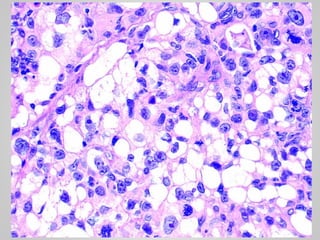

• Well-differentiated liposarcoma

• Adipocytes with scattered atypical spindle cells

• 12.

LIPOSARCOMA • One ofthe most common sarcomas of adulthood • People in their 50s to 60s • Deep soft tissues of the extremities and in the retroperitoneum • Amplification of MDM2 gene

• 13.

• Well-differentiated liposarcoma •Adipocytes with scattered atypical spindle cells • Myxoid liposarcoma • Abundant basophilic extracellular matrix, arborizing capillaries and primitive cells at various stages of adipocyte differentiation • Pleomorphic liposarcoma • Sheets of anaplastic cells, bizarre nuclei and variable amounts of immature adipocytes (lipoblasts).

• #19 Pleomorphic liposarcoma